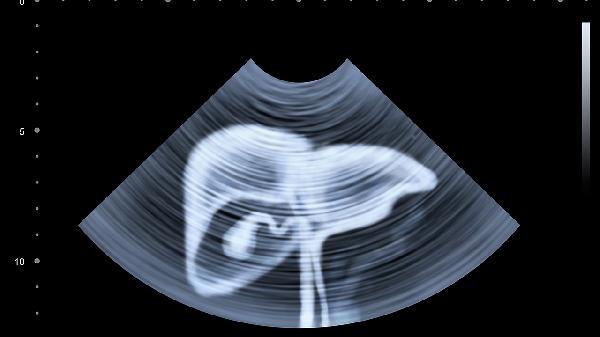

肝脏代谢胆红素障碍时会导致黄疸,表现为巩膜和全身皮肤发黄,可能伴随皮肤瘙痒。这种情况常见于急性肝炎、胆管梗阻等疾病,需通过肝功能检测和腹部超声明确病因。治疗可选用茵栀黄颗粒、熊去氧胆酸片等药物,同时需限制高脂饮食。

维护肝脏健康需保持规律作息与均衡饮食,每日摄入30克优质蛋白如鸡蛋清、豆腐等,限制腌制和霉变食物。建议40岁以上人群每年检查肝功能与肝脏超声,乙肝病毒携带者每3-6个月监测病毒载量。出现持续乏力、食欲下降等非特异性症状时,应及时排查肝脏疾病可能。